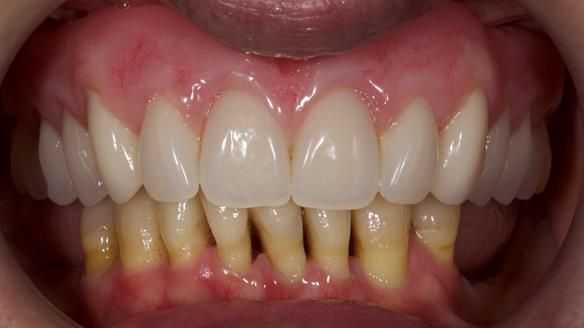

She had previously suffered from generalised periodontitis – stage IV, grade C, currently stable, with reduced attachment across the upper arch.

By the time she came to me, her periodontal condition was stable — but the aesthetics in the upper jaw were very poor.

We provided her with an immediate upper denture (Mk 1), followed by a definitive metal-based upper denture (Mk 2). A lower removable partial denture was discussed, to be made only if needed once the upper treatment was complete. However, at review, this wasn’t necessary — Adnana had excellent neuromuscular control and function, even with a shortened dental arch (SDA).

Rowan, Sam Hesketh and Chris Hesketh provided the stunning technical work. I am very lucky to have them.

- A restored smile, restored lip support, and a patient who owned the journey